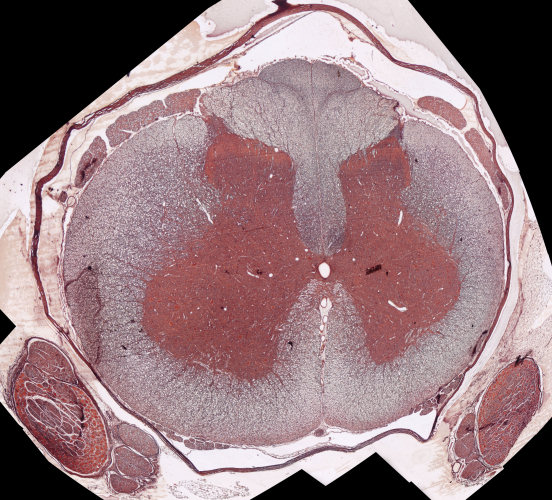

back Dwarssnit deur die rugmurg

Identifiseer die volgende dele op die dwarssnit van die rugmurg: / Identify the following parts on the cross section of the spinal column:

Grysstof / Grey matter

Witstof / White matter

Spinaalganglion / Spinal ganglion

Sentrale kanaal / Central canal